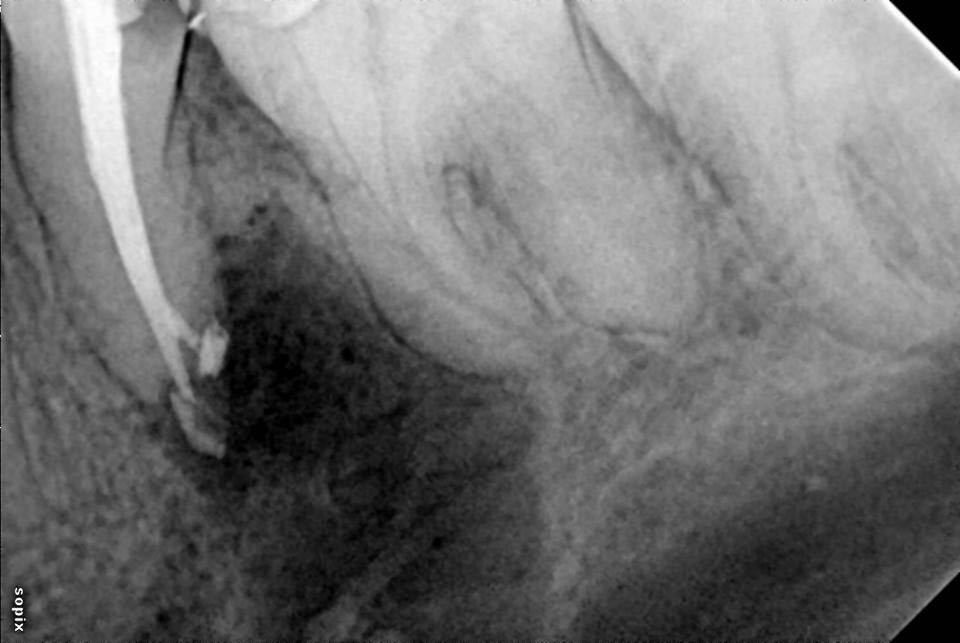

左下第二前磨牙根管再治疗

转自FB.根管再治疗,5个月随访,病变愈合良好。